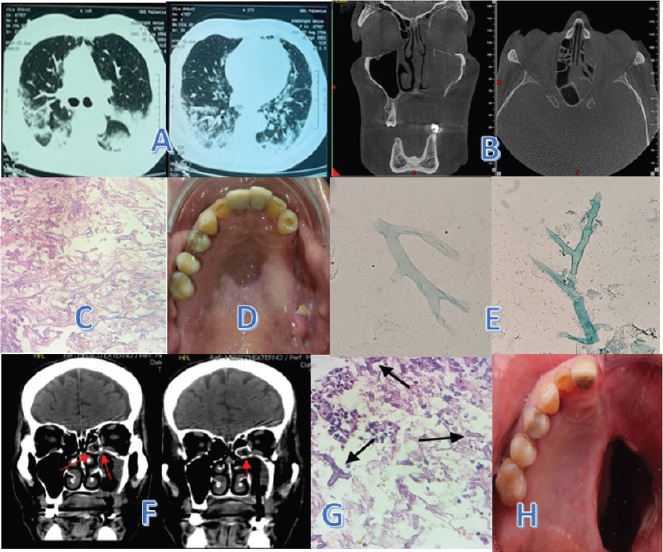

Fig. 1 (A) 02/04/2021. TAC de tórax, focos neumónicos con signo de halo invertido, signos de vidrio esmerilado bibasales a predominio derecho, engrosamiento intersticial sugestivo de fibrosis pulmonar. (B) 10/04/2021. TAC craneal, imagen hiperdensa en seno maxilar izquierdo extendida a celdillas etmoidales izquierdas, cornetes nasales superior, medio e inferior izquierdo y seno esfenoidal izquierdo. (C) 20/05/2021. Estudio histopatológico, extensa necrosis de tejido blando y óseo, severo infiltrado inflamatorio mixto y presencia de hifas grandes, abundantes, prominentes, no tabicadas y ramificadas, diagnósticas de mucormicosis. Tinción: Hematoxilina y eosina (HE), 20X. (D) 22/05/2021. Cavidad oral posterior a: odontectomías, debridamiento quirúrgico, cierre de la comunicación bucosinusal y estudio histopatológico (E) 26/05/2021. Microscopía directa con KOH: hifas hialinas, no tabicadas, gruesas, tortuosas, algunas acintadas, ramificadas en ángulo recto. (F) 12/06/2021). TAC craneal, reducción de la lesión del seno paranasal y de la comunicación oroantral izquierda; compromiso de: maxilar, etmoides y esfenoides, septo y piso de la órbita. Del tiempo postoperatorio: (G). 16/06/2021. Estudio histopatológico sobre muestra obtenida en el momento quirúrgico: hifas grandes, algunas acintadas, no segmentadas, ramificadas. Tinción: HE, 40X. (H) 18/09/2021. Cavidad oral tres meses después del momento quirúrgico.

El día 20/03/2021 presenta escalofríos, disnea progresiva, fiebre y tos y solo un día expectoración marrón. Un Médico Internista (en CSP), realiza el diagnóstico de la COVID-19 (diagnóstico clínico inicial sin pruebas de laboratorio) y prescribe tratamiento ambulatorio con levofloxacina, polivitaminas, aspirina infantil; también, dexametasona 4 mg cada 8 horas por tres días y adicionalmente metilprednisolona cada 8 horas por dos días, posterior a lo cual hace estado hiperglicémico (500 mg/mL), sin cetosis, que se controló después de 10 días. Recibe oxígeno húmedo con bigote nasal durante una semana, administrado con agua envasada en botellón, mismo medio empleado en la nebulización (budesonida, alternativamente con solución 0,9%). Los síntomas de la COVID-19 cedieron al cabo de 15 días, con prueba antigénica tardía negativa y serología positiva para inmunoglobulina G. La TAC (Tomografía Axial Computarizada) de tórax del 02/04/2021 presentó focos neumónicos con signo de halo invertido, signos de vidrio esmerilado bibasales a predominio derecho y de fibrosis pulmonar (Fig.1A). La evidencia combinada, clínica, radiológica y de laboratorio, en ese momento epidemiológico, se consideró consistente con la COVID-19.

Acude a Odontología General (CSP) el 08/04/2021, donde se realiza drenaje de abscesos en la región vestibular maxilar izquierda y se instaura tratamiento con clindamicina, amoxacilina/clavulánico y pregabalina. Se ordena realizar ortopantomografía. También consulta a Otorrinolaringología (CSP), donde se le diagnostica sinusitis. La TAC de cráneo (10/04/2021) describe imagen hiperdensa del seno maxilar izquierdo extendida a celdillas etmoidales izquierdas, cornetes nasales superior, medio e inferior izquierdo y seno esfenoidal izquierdo (Fig.1B).

Sin presentar mejoría, el 20/05/2021 consulta al Servicio de Cirugía Bucal y Maxilofacial del Hospital Universitario “Dr. Ángel Larralde “- Instituto Venezolano de los Seguros Sociales (HUAL -IVSS), donde los especialistas describen aumento de volumen de la hemicara izquierda, con dolor pulsátil irradiado al ojo izquierdo. Al proceder a la odontectomía de las estructuras móviles 25, 26 y 27, junto con ellas se desprende espontáneamente un fragmento del hueso maxilar (tabla vestibular y palatina). Bajo la impresión diagnóstica de seno maxilar ocupado (la ortopantomografía mostraba velamiento del seno maxilar izquierdo) y osteonecrosis maxilar, se toma la biopsia para estudio histopatológico. El Laboratorio de Patología Bucal y Maxilofacial (laboratorio independiente, sector privado) describe al examen microscópico (20/05/2021): extensa necrosis, tanto de tejido blando y como de tejido óseo, severo infiltrado inflamatorio mixto a predominio mononuclear y presencia de hifas grandes, abundantes, prominentes, no tabicadas y ramificadas, diagnósticas de mucormicosis (Fig.1C).

El día 25/05/2021, en consulta con Medicina Interna/Infectología del HMN (referido por el HUAL -IVSS), el paciente se presenta en buenas condiciones generales, con dolor a la digitopresión sobre la región malar izquierda y con un soplo grado II/IV en el foco aórtico, como todo dato positivo al examen físico. Al no observarse lesiones sugestivas de mucormicosis, según los criterios clásicos de Smith y Krichner citados 8, en las áreas intervenidas en la cavidad oral o adyacentes (Fig.1D), se ordena repetir el estudio micológico y el 26/05/2021, el Laboratorio de Micología y Enfermedades Tropicales (laboratorio independiente, sector privado) realiza examen directo y cultivo en muestras del área de las odontectomías, del maxilar y de la fosa nasal izquierdos, dando como resultado mucormicosis en tejido del seno maxilar izquierdo.

El reporte del Laboratorio Micológico detalla: a) Sobre la muestra del tejido maxilar, bajo microscopía directa con KOH se observaron moderadas hifas, hialinas, cenocíticas (no tabicadas), gruesas, tortuosas, algunas acintadas, ramificadas en ángulo recto (Fig.1E). Igual imagen se apreció en el extendido con tinción de Giemsa, donde además se reportaron escasos polimorfonucleares neutrófilos, escasos linfocitos, escasos macrófagos, escasa microbiota bacteriana de morfología mixta y no se observaron formas micóticas intracitoplasmáticas. Al examen directo con tinta china (tinción al negativo) no se observaron formas micóticas capsuladas. El cultivo de la muestra reveló desarrollo repetitivo del hongo con aspecto filamentoso, Rhizopus spp. Y b) Sobre la muestra del tejido de fosa nasal izquierda, al examen directo con KOH y con tinta china, no se observaron formas micóticas; en el extendido con Giemsa se observaron escasas células (polimorfonucleares neutrófilos, linfocitos, macrófagos), sin presencia de formas micóticas. Luego de cinco días de incubación, no hubo desarrollo de hongos en el cultivo.

El 12/06/2021 se repite la TAC de cráneo donde se observa reducción de la lesión del seno paranasal y la comunicación oroantral izquierda, pero siguen tomadas áreas (Fig.1F) del maxilar, etmoides y esfenoides, además del septo -desviación mixta-, con compromiso del piso de la órbita.

El estudio microscópico sobre las muestras obtenidas en el momento quirúrgico resultó negativo al estudio micológico, tanto al examen directo como en cultivo, mientras el estudio histopatológico detectó todavía el hongo en el tejido examinado (Fig.1G). Los exámenes micológicos y de histopatología fueron realizados por los mismos observadores y laboratorios que efectuaron el diagnóstico inicial y participaban del seguimiento del caso. Los detalles fueron los siguientes:

En el postoperatorio mediato y tardío, el paciente mantuvo controles médicos integrales (HUAL -IVSS y HMN) a ritmo de tres, seis y doce meses, con una evolución favorable (Fig.1H). Se destaca: i) Al finalizar el tratamiento con anfotericina B, inició voriconazol a razón de 400 mg cada 12 horas como dosis de impregnación y luego 200 mg cada 12 horas, de mantenimiento, durante 1 mes. ii) Seis semanas después de la cirugía, en fase de rehabilitación, se le colocó una prótesis obturadora removible sujeta a sucesivos ajustes. iii) El 24/02/2022, sobre hisopado de las fosas nasales y del seno maxilar, el estudio micológico informó la no presencia de hongos al examen directo con KOH, examen directo con tinción de Kane negativo para bacterias y cultivo micológico a 28°C sin desarrollo de hongos, hasta los 30 días de incubación. iv) El 18/04/2022 se realiza RMN de control, la cual reporta reducción del tamaño del antro maxilar izquierdo, así como ausencia de cornetes izquierdos y de la arcada dentaria del maxilar izquierdo, en correlación con antecedente quirúrgico. Paredes orbitarias indemnes, con aspecto irregular del piso de la órbita izquierda; sin evidencia de lesiones de los globos oculares. Se planifica la reconstrucción del área intervenida y se prepara al paciente para realizar el cierre de la comunicación oroantral empleando un colgajo del músculo temporal y la reconstrucción maxilar con implantes cigomáticos, lo cual se programa para el mes de octubre de 2022.